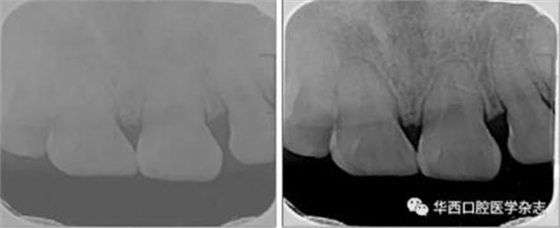

(2)X線片可調(diào)整灰度進(jìn)行動(dòng)態(tài)對(duì)比審閱。如圖2所示,同一張X線片經(jīng)灰度調(diào)整后,清晰顯示根折影像。

左:疑似根折;右:可見明顯根折。

圖 2 X線片不同灰度值的對(duì)比結(jié)果